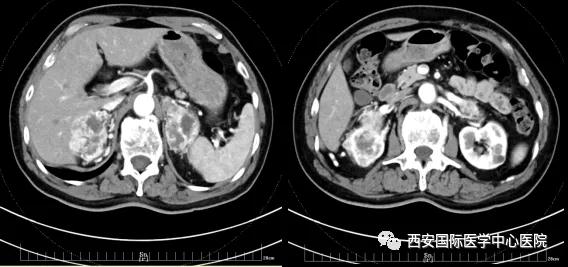

今年七十五歲的患者,來自陜西省商洛市,四月前因腰背部疼痛就診于當(dāng)?shù)蒯t(yī)院,行CT檢查發(fā)現(xiàn)“右腎、雙側(cè)腎上腺占位,前縱膈淋巴結(jié)腫大,雙肺多發(fā)結(jié)節(jié)、胸椎骨質(zhì)破壞,考慮轉(zhuǎn)移瘤”。為進(jìn)一步診斷治療,患者的兒子帶他來到西安某三甲醫(yī)院,查泌尿系CT提示“右腎占位性病變,多考慮腎癌,雙側(cè)腎上腺多發(fā)轉(zhuǎn)移灶,腹膜后多發(fā)腫大淋巴結(jié)”;行穿刺活檢提示“腎透明細(xì)胞癌”;并給予患者口服靶向藥物的治療方案。

自四月份至今,患者一直口服靶向藥物治療(阿昔替尼5mg 2次/日),期間無不良反應(yīng),目前腰背部疼痛癥狀也有所緩解,復(fù)查影像學(xué)資料提示瘤體較前縮小,腫瘤完整切除的可能性明顯提高;而且患者的兒子也是一名外科醫(yī)生,所以他更想為父親完成后續(xù)的手術(shù)治療。

手術(shù)由楊增悅教授主持,舒濤主治醫(yī)師、王東主治醫(yī)師主刀,黃怡醫(yī)師、王平醫(yī)師協(xié)助完成。由于第四代達(dá)芬奇機(jī)器人更加靈活和精準(zhǔn)的特性,手術(shù)全程順利,尤其是完全精準(zhǔn)的“解鎖”了右腎動(dòng)脈和右腎靜脈的數(shù)十根交互纏繞的分支血管。術(shù)后患者麻醉恢復(fù)后生命體征平穩(wěn),順利返回泌尿外科普通病區(qū)進(jìn)一步康復(fù)。